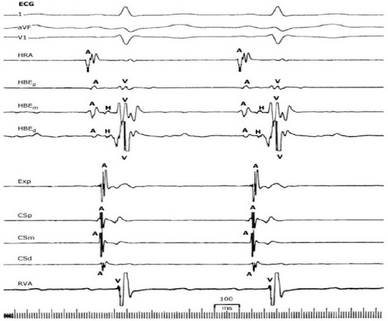

Em relação ao eletrograma abaixo. é correto afirmar que:

Legenda: 1= derivação DI; aVF e V1 = derivações do eletrocardiograma; HRA = derivação atrial alta; HBE = eletrodo no sistema His (p = proximal; m = médio; d = distal); Exp = eletrodo exploratório; CS = eletrodo no seio coronário (p = proximal; m = médio; d = distal); RVA = eletrodo no ventrículo direito; A = registro atrial; H = registro em His; V = registro ventricular.